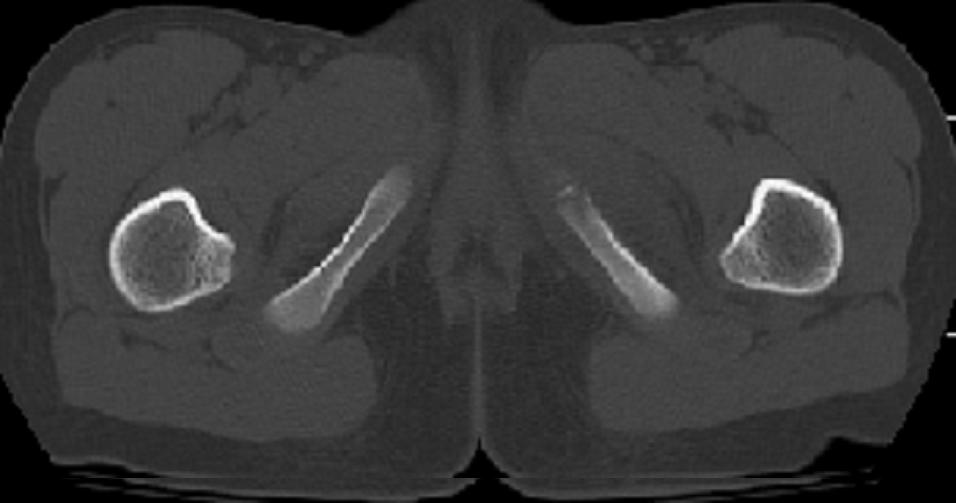

以下是引用zxd95在2008-7-2 10:06:00的发言:[br]左耻骨下支局部骨质破坏,内见小条状小骨片,周围肌间隙模糊,左闭孔内外肌肿胀。[br]儿童患者,首先考虑结核性,以骨质破坏为主(其内小条状小骨片解释为死骨)。[br]鉴别:[br]1、化脓性病变以增生为主;[br]2、肿瘤性病变:良性肿瘤不会有周围软组织的肿胀、模糊;恶性肿瘤病变骨皮质破坏、中断;[br]3、肿瘤样病变:一般也无周围软组织的改变。[br]建议查肺部及结核相关实验室检查。

以下是引用dyqct在2008-7-2 15:38:00的发言:[br]左坐骨与耻骨交界处膨胀性溶骨性病变,周围软组织略肿胀,边界不清。[br]发生在这个年龄组该部位最常见的一种发育变异,可以出现此种改变。另外感染不除外,建议定期复查。